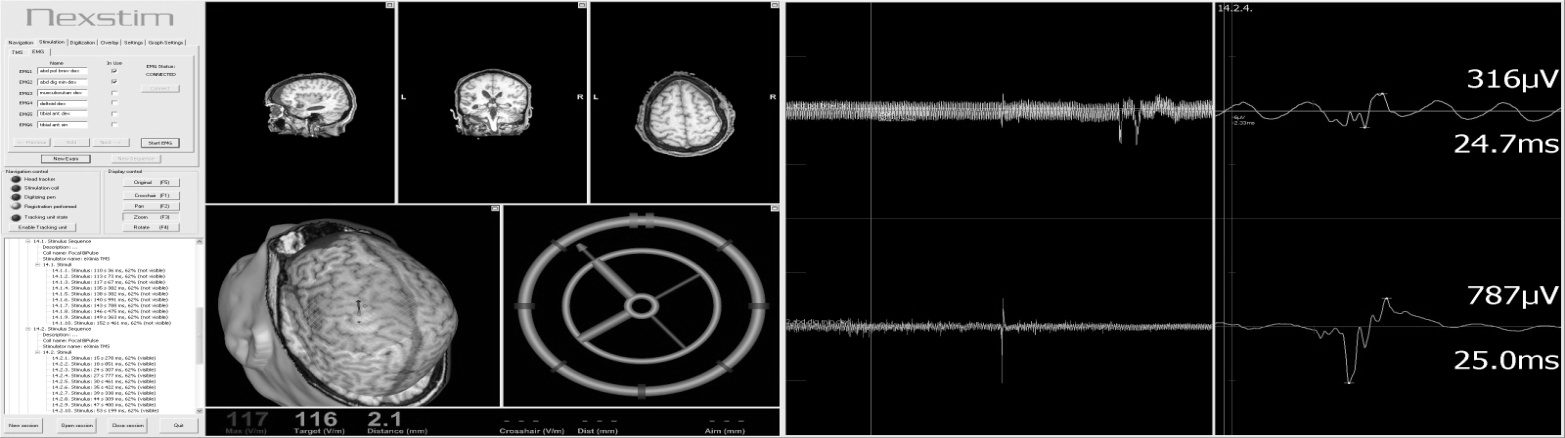

In our practice we use patented method7 of CMD detection based on navigated brain stimulation which is called NBS-CMD-test. The principle of method is following: first step is mapping of individual localization of motor cortical zones via NBS, in our protocol it was zone responsible for musculus abductor pollicis movements (Figure 1). Secondly this motor zone was stimulated with magnetic stumuli: 10 of them were provided without any facilitation and next 10 were accompanied with an audial command, ordering patient to raise his hand. Then all the amplitudes of received motor responses, registered with myographic tracking, were averaged out. In case averaged amplitude of facilitated stimuli exceeds non-facilitated amplitude by more than 20%, the result of NBS-CMD-test was ranked as a positive. That meaned, that clinically unresponsive patient heard an audial command, understood it and tried to execute it, but failed due to neurological deficit. Thus, we concluded that positive result of NBS-CMD-test indicates the presence of CMD in such a patient.

Figure 1 Upper extremity motor cortical representation.

Evoked motor responses with >1000 mkV amplitude are marked with white dots; 500-1000 mkV – yellow dots, 50-500 mkV – red dots; <50 mkV or without myographic response – grey dots.